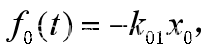

这种给药方式相当于在药物进入中心室以前,先有个将药物吸收入血液的过程,可以简化为一个吸收室,如图15所示,x0(t)是吸收室的药量,药物由吸收室进入中心室的速率为k01。

吸收室药量满足 【4.8】

【4.8】

将【4.8】代入 得到

得到 【4.9】